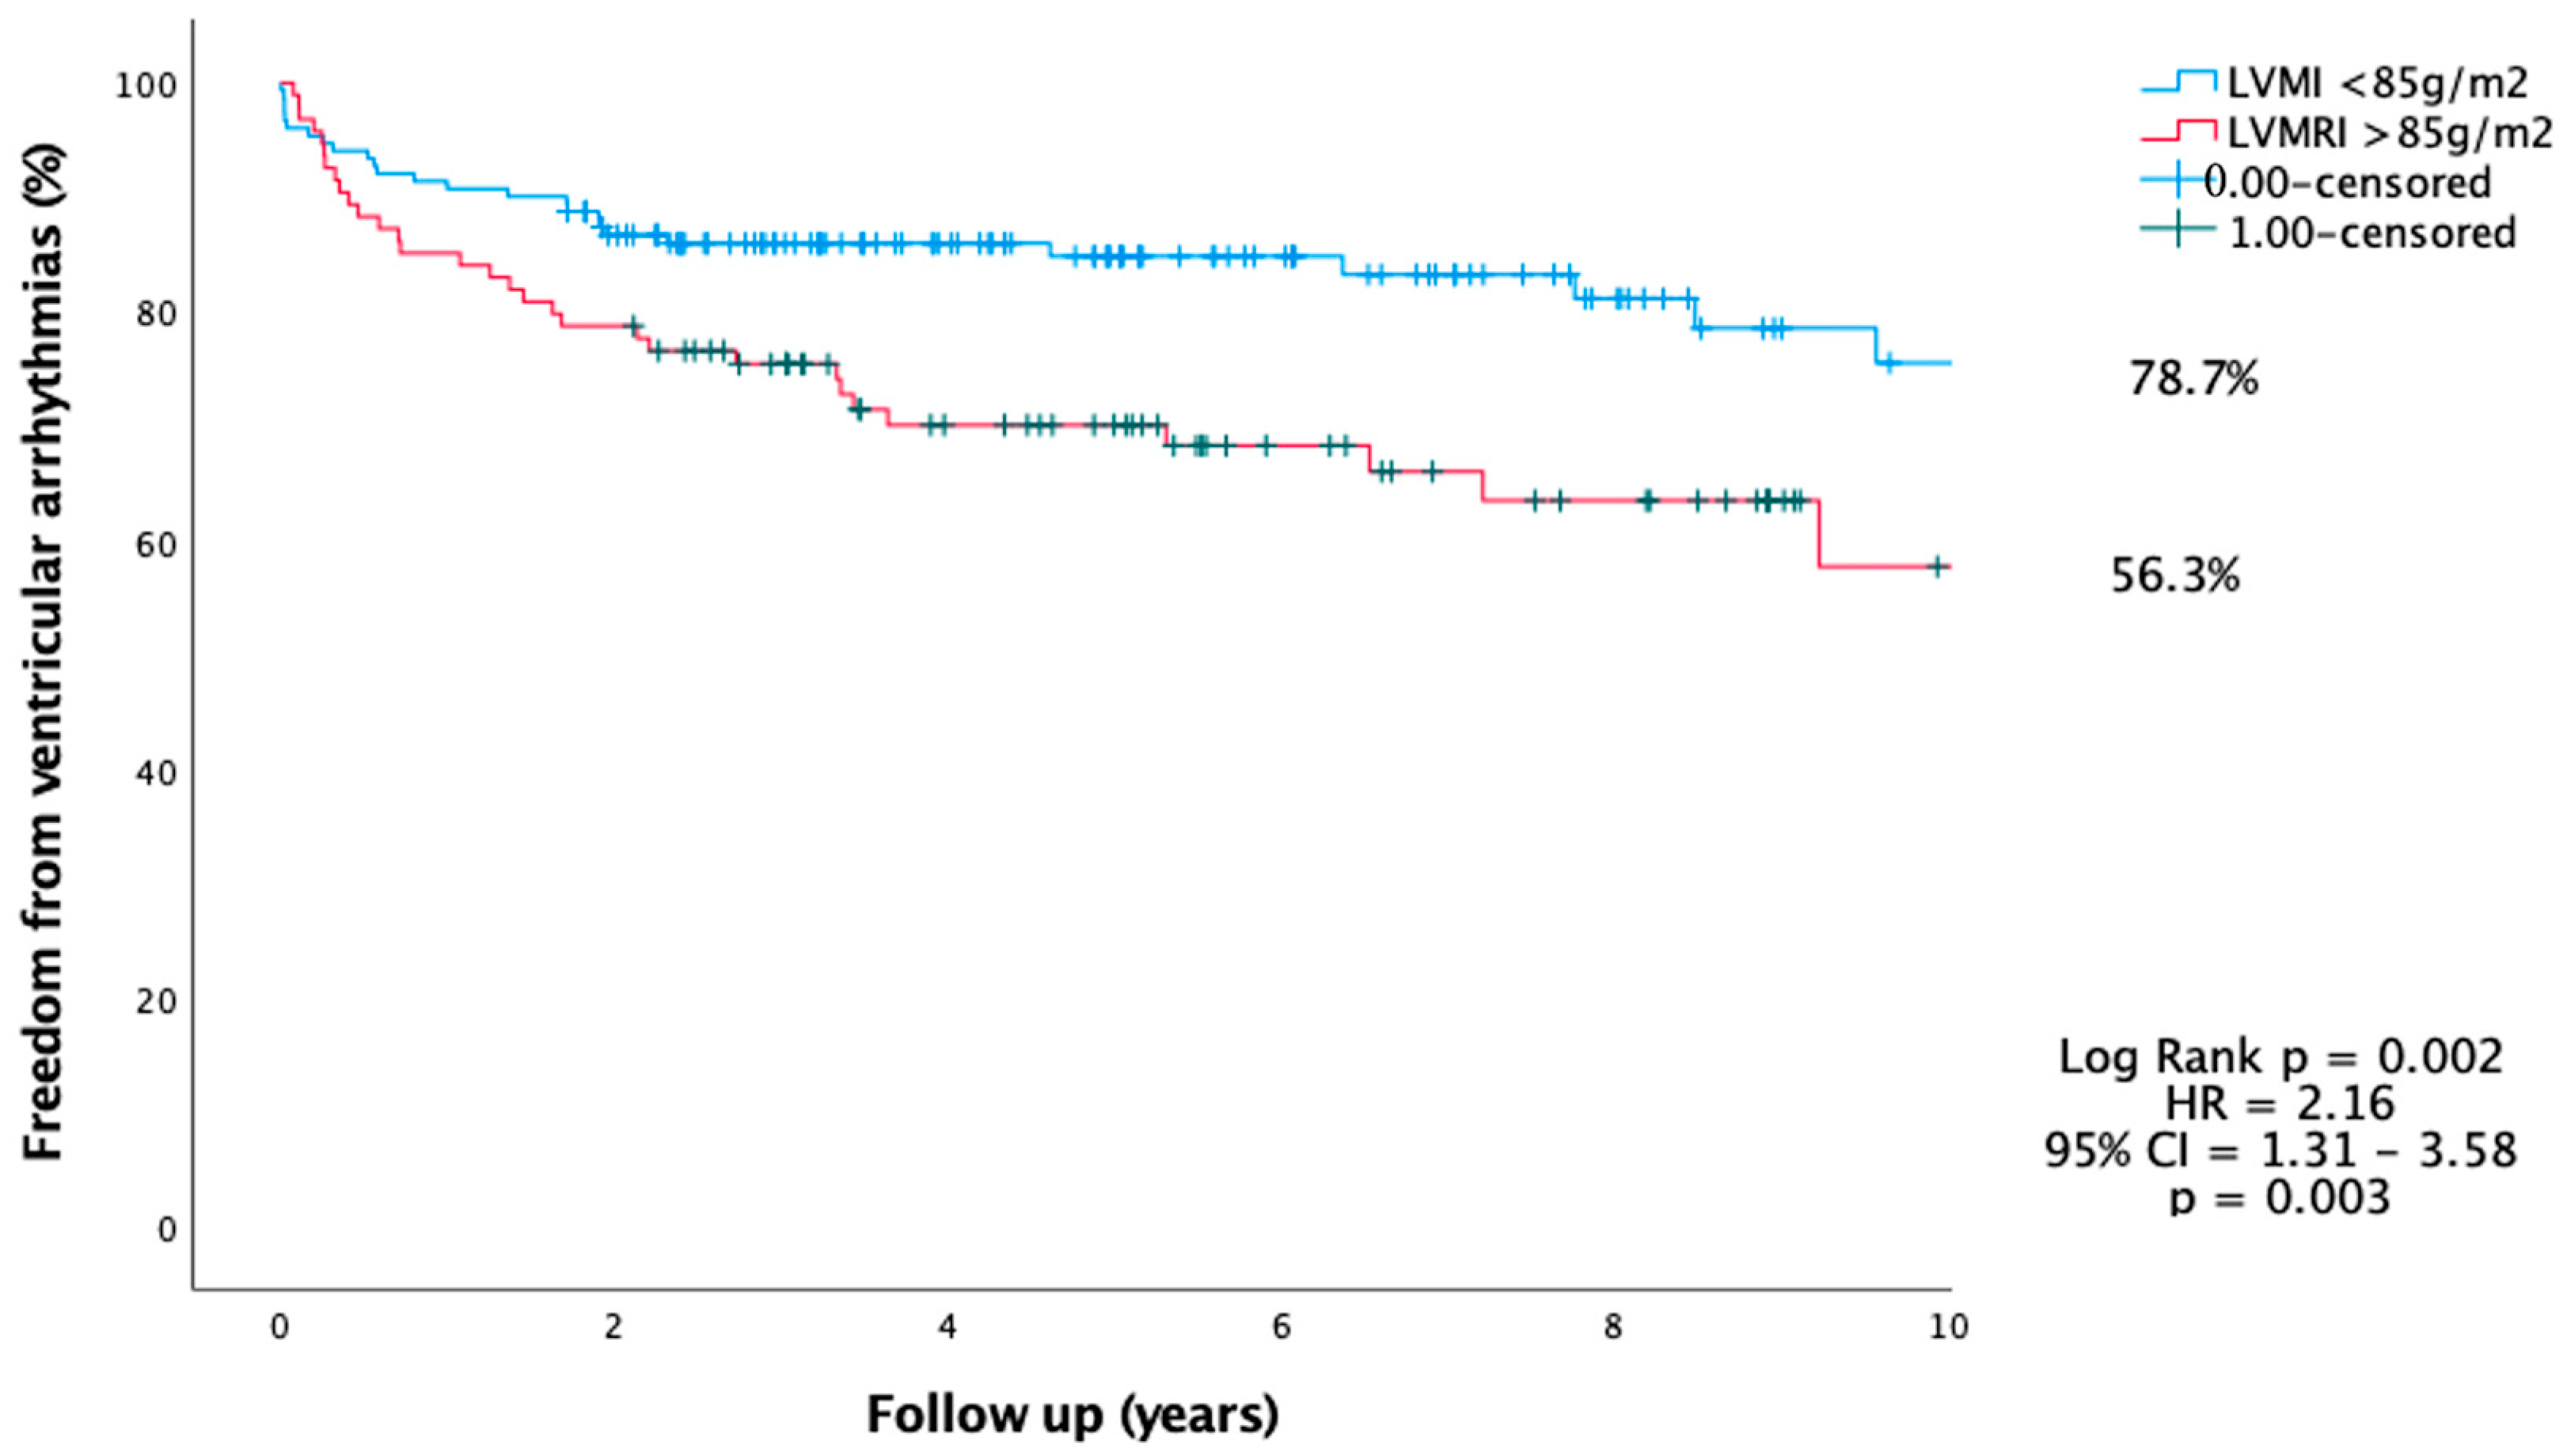

6.2. Predictors of VT

- Higher LVMI is associated with VA and can be considered for risk stratification of SCD in HCM.

- LVMI > 85 g/m2 and LVLGE > 6% are associated with VA.

- LVMI and LVLGE were independent predictors of VA during follow-up.